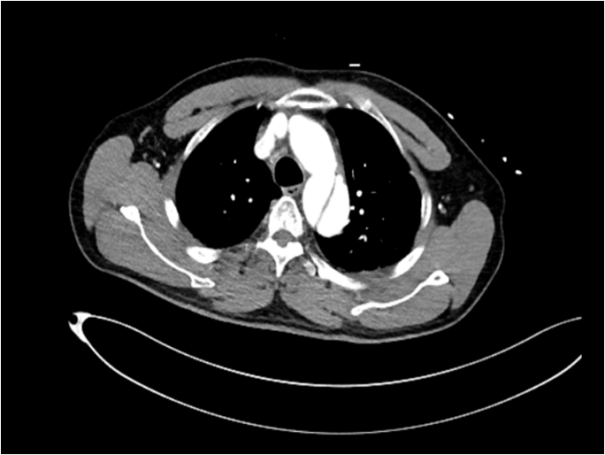

48岁男性,突发上腹剧烈疼痛伴有大汗淋漓,既往多年高血压病史。

时间就是生命。医生会结合症状,快速进行以下检查:医院会根据CT血管成像(CTA)进行诊断。如确诊为主动脉夹层,则会进行紧急处理,立即镇痛、控制血压和心率(如静脉注射β受体阻滞剂)。

A型夹层:开放手术

手术是“巨创手术”,需要在深低温停循环下,用人工血管替换掉被撕裂的主动脉段,就像换掉一段坏掉的水管。手术风险高,但这是唯一能救命的方法。